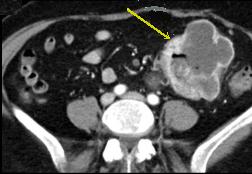

Leiomyomesarcoma de l'intestin

: Tumeur a polylobulaire homogene a hypo-dense de la

paroi de l'intestin . La lumiere de l'intestin est

peu serre . Nodule de calcifie en se voyait ( fleche

jaune ) . Image radiologique TDM en coupe axiale a

travers region pelvienne |